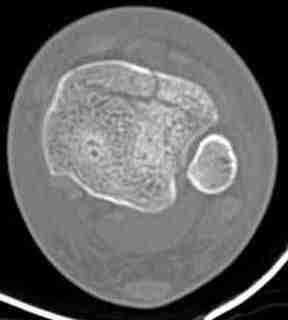

КТ пилона имеем.

Предыдущей сменой до 4:00 утра по поводу открытого перелома бедра, тибиал плато, пилон и надколенника сделана операция.

Пострадавшему 21 г., травма скоростная, после I&D с расширением раны, на бедре сделана операция ретроградным интрамедуллярным штифтом, остеосинтез с частичной резекцией надколенника и ушивание собственной связки.

В настоящее время больной в реанимации по поводу Черепно Мозговой Травмы и состояние улучшается. Запланировал ушивание раны в пятницу, если позволит состояние мягких тканей и при отсутстви отека возможно удастся просунуть перкутанномедиальную пластину.